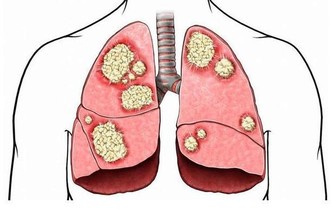

氣與血是人體內的兩大類基本物質,氣血的調和與通暢是人體健康的關鍵。氣血不足者,往往出現神倦乏力,氣短心悸,陰虛津少,口乾舌燥,臉色萎黃無神,說話有氣無力等症狀。氣血不足,為健康埋下了巨大的隱患,導致免疫力下降,難以抵擋病邪入侵。補好氣血,提升免疫力,是防止亞健康人群患上疾病的一條重要途徑。